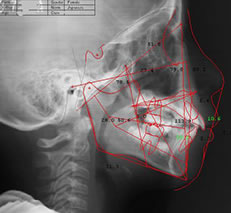

当院では、矯正治療に特化したレントゲン技術である「セファロ」を導入しています。この装置は、歯や顎だけでなく、頭部の正面と横からの撮影が可能です。

これにより、歯をどのように移動させるかを具体的に計測し、治療の精度を向上させることができます。